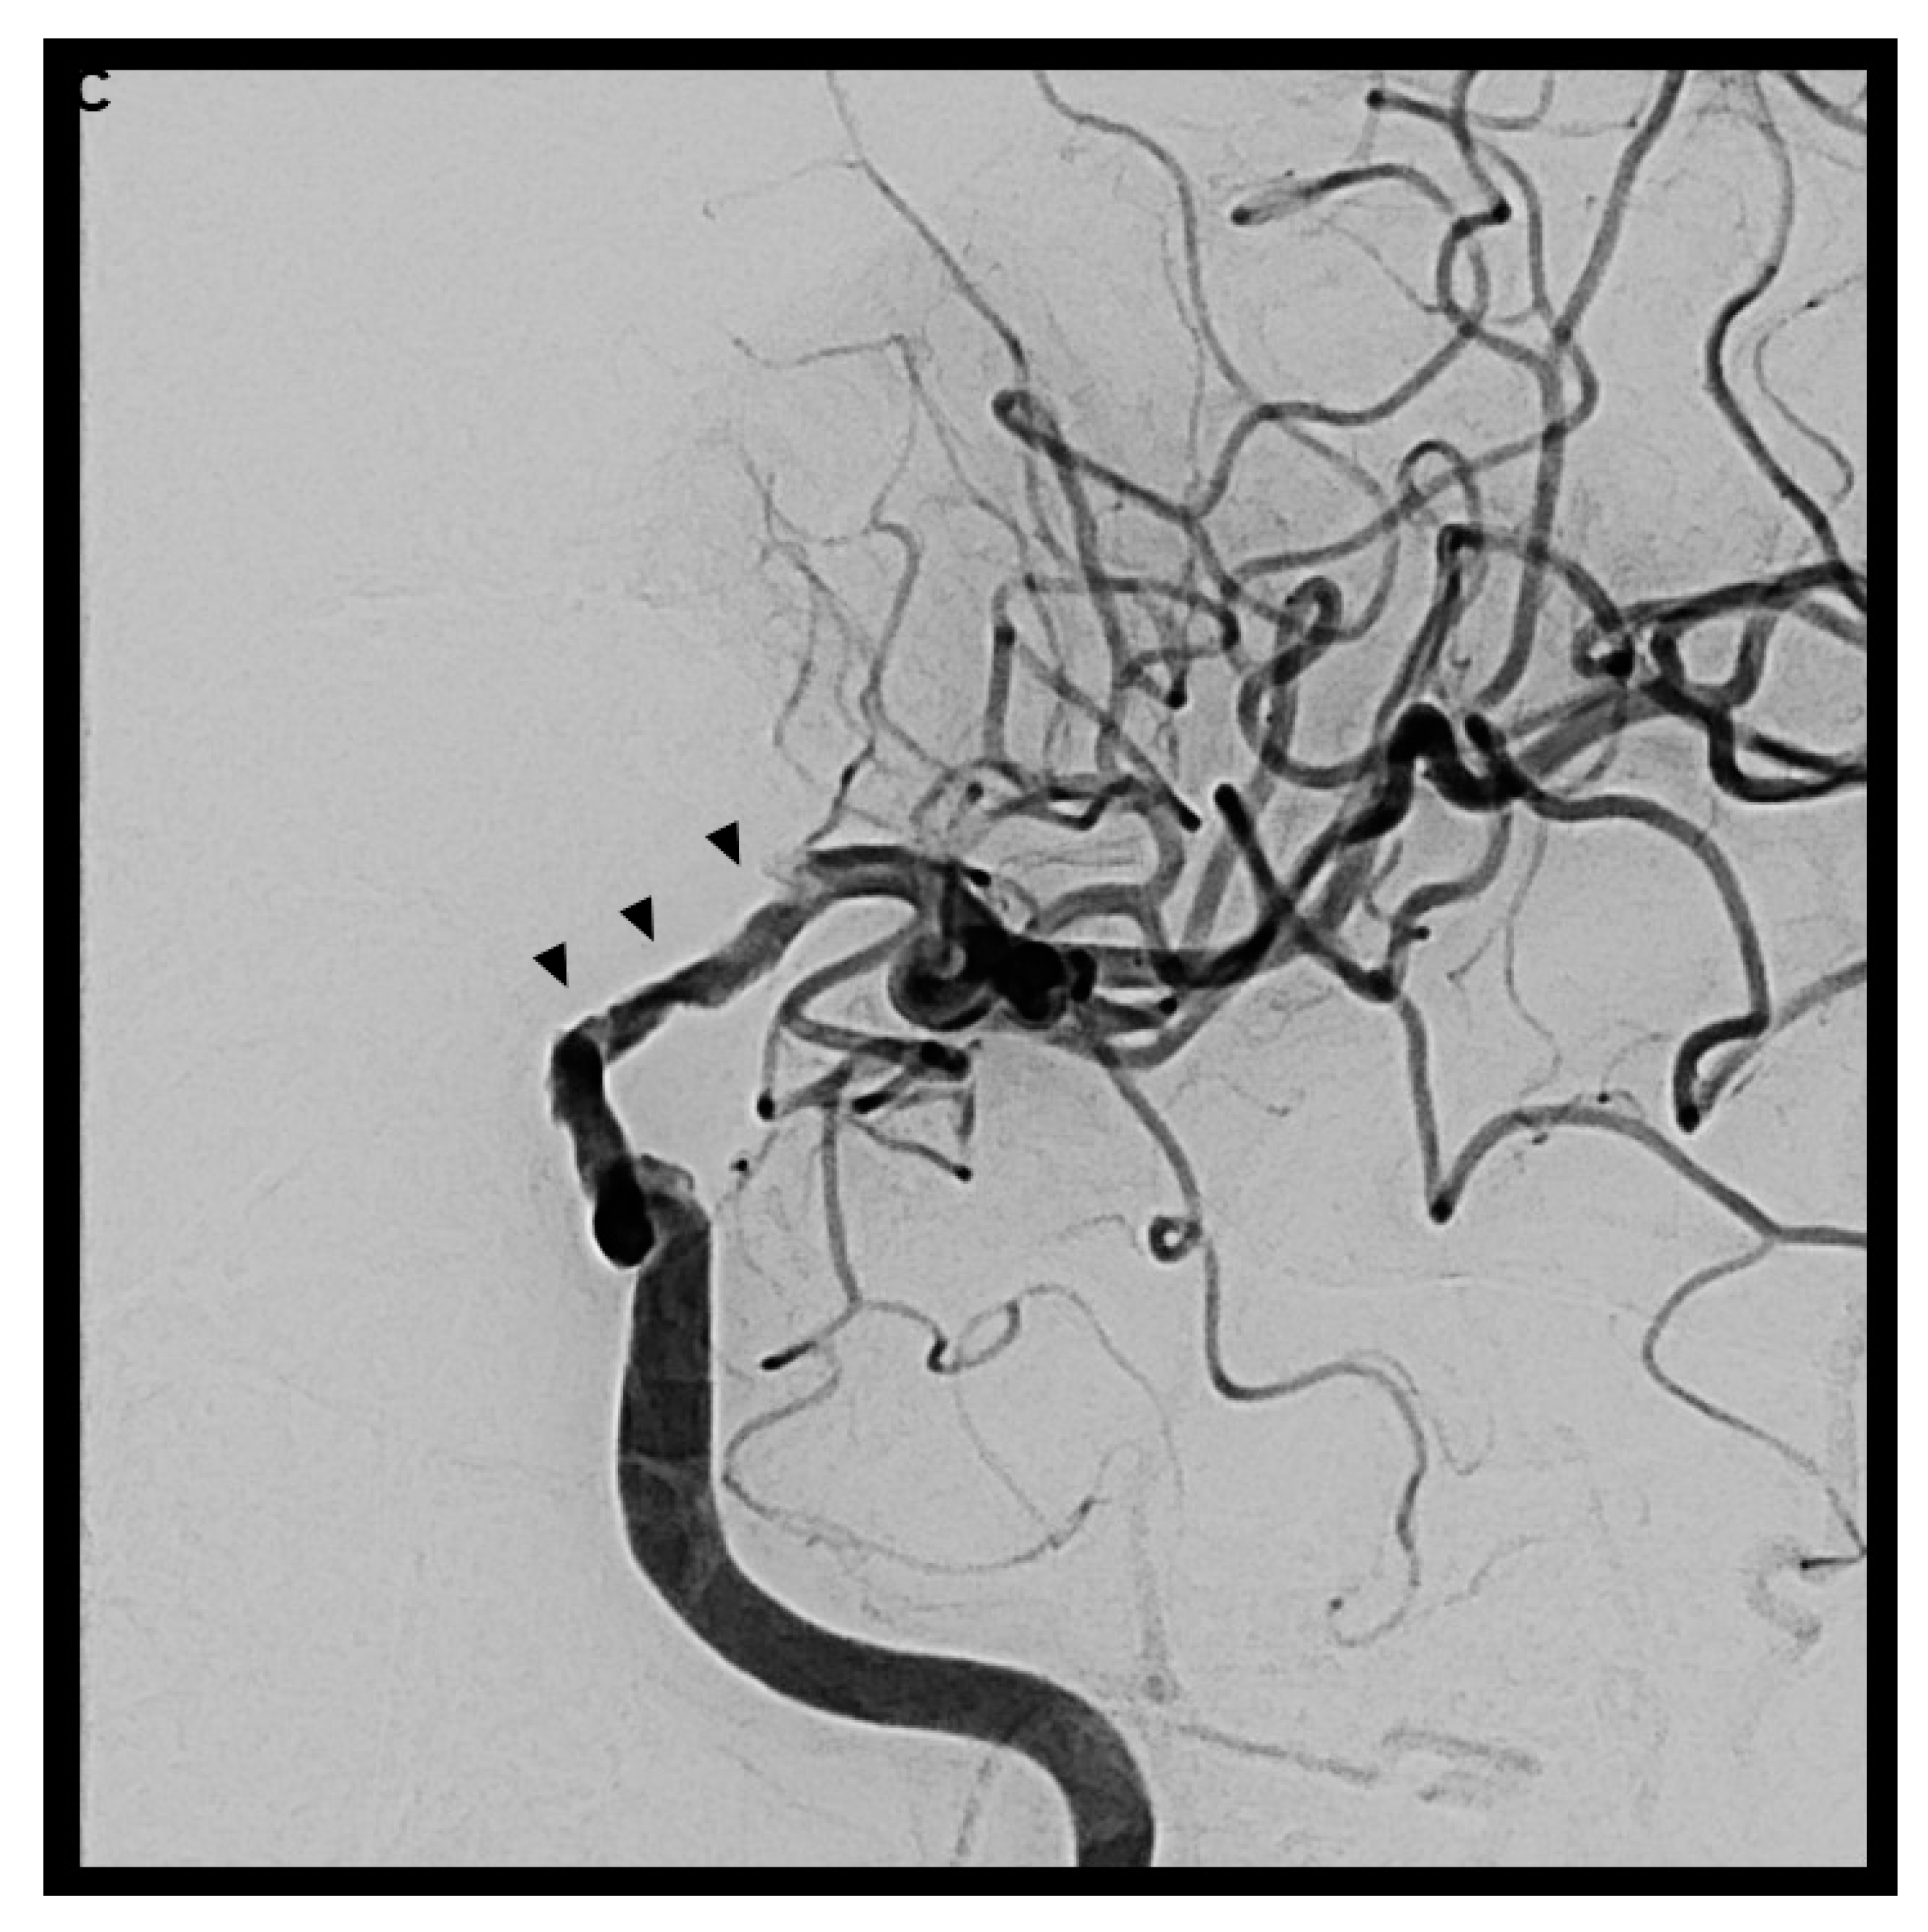

The patients experienced further clinical deterioration marked by decreased vigilance, worsening aphasia, and intensified right-sided hemiparesis, resulting in an NIHSS of 15 points. On day 7 after initial presentation at the first hospital (day 11 after symptom onset), the patient was transferred to our university clinic and admitted to our neurological intensive care unit (NICU). MRI was repeated, showing unchanged local inflammatory changes; however, new vessel abnormalities as well as diffusion restriction in the left middle cerebral artery territory were observed (Figure 5A,B). Based on these findings and the differential diagnosis of vasculitis or vasospasm, a digital subtraction angiography (DSA) was performed (Figure 5C).

Figure 5.

Diffusion-weighted imaging in cerebral MRI showed now new areas of ischemia within the middle cerebral artery territory (A). Further evaluation with cerebral MR Angiography (B) revealed new, compared to earlier imaging a few days before, irregularities in the vessel walls of the left intracranial internal carotid artery, with moderate-to-severe luminal narrowing. To clarify these findings, Digital Subtraction Angiography (DSA) was performed (C). The DSA indicated that while the extracranial segment of the left internal carotid artery appeared normal, significant irregularities were present beginning at the petrous segment. These irregularities (black arrows) caused moderate luminal narrowing with partial filling of the middle cerebral artery from crossflow via the A1 segment. During the venous phase, adequate contrast filling of the cavernous sinus was observed, effectively ruling out a cavernous sinus thrombosis. Despite local administration of 3 mg Nimodipine over 30 min, there was no alteration in the observed vascular irregularities, supporting the conclusion that these changes were inflammatory rather than spasmodic.